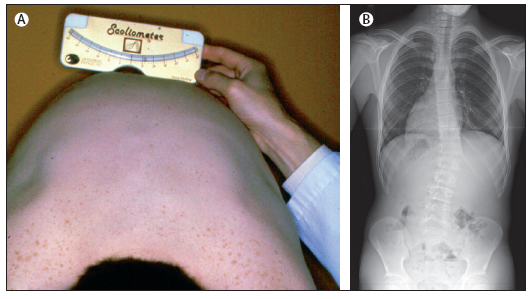

Figura

2. Comparsa del gibbo all'inizio (A) e alla fine (B) della

flessione anteriore (G. Bartolozzi, Guglielmi M. Pediatria, Principi

e pratica clinica, Elsevier 2008, pag. 1233)

La SIA è

una curvatura strutturale, laterale e con rotazione della

colonna che colpisce soggetti adolescenti, peraltro sani, durante la

pubertà. La diagnosi è di esclusione ed è

fatta soltanto quando altre cause di scoliosi, come le malformazioni

vertebrali, le malattie neuromuscolari e i quadri sindromici siano

stati esclusi. Lo screening sugli adolescenti va effettuato

attraverso la manovra di Adam (un chirurgo inglese vissuto alla fine

dell'Ottocento) in flessione anteriore e con uno scoliometro,

sebbene una diagnosi definitiva possa essere posta solo dopo la

valutazione dell'angolo di Cobb in una radiografia, eseguita

frontalmente (Figura 1 e Figura 2).